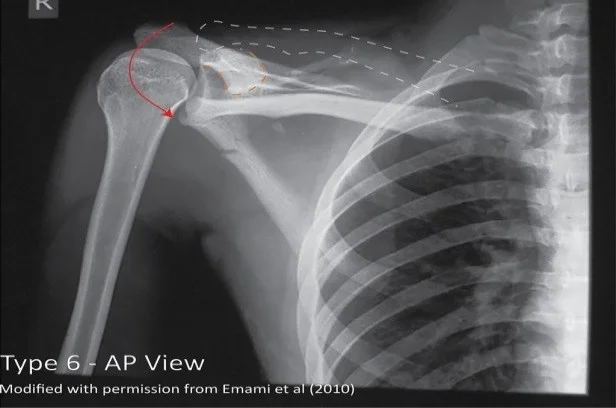

Acromioclavicular Joint Injury: Rockwood Classification

Acromioclavicular joint injuries are characterized by the degree of damage to the AC ligament and the CC ligaments. (3). These injuries are further classified using the Rockwood System (Figure 6).

| Type VI | AC Ligament Rupture |

| ![]() |

Urgent orthopedic referral is indicated in patients with neurovascular compromise, skin tenting, and significant deformity. Additionally, Type IV-VI AC injuries are typically managed surgically and, as such, require urgent orthopedic consultation.

Type VI: Case courtesy of Dr Jeffrey Hocking, <a href="https://radiopaedia.org/">Radiopaedia.org</a>. From the case <a href="https://radiopaedia.org/cases/48600">rID: 48600</a>